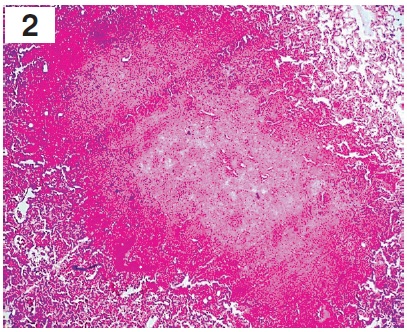

Рисунок 3. Микроскопическая картина тотальной абсцедирующей пневмонии: некротические участки с расплавлением альвеолярной ткани, множественными кровоизлияниями, в альвеолах определяется геморрагический и серозный экссудат с инфильтрацией мононуклеарными лейкоцитами. Окраска гематоксилином и эозином (×900) / Figure 3. Microscopic picture of multiple hemorrhages in the alveoli with mononuclear leukocyte infiltration. Stained with hematoxylin and eosin, ×900

В легких были выявлены признаки двусторонней тотальной геморрагической пневмонии. При макроскопическом исследовании: легкие с двух сторон плотной консистенции, тяжелые, безвоздушные, отечные, синюшного цвета. При гистологическом исследовании определялись неравномерно расправленные альвеолы с утолщенными межальвеолярными перегородками за счет отека и полнокровия, признаки пролиферации эндотелиоцитов капилляров, десквамация альвеолярного эпителия, отек, мононуклеарная инфильтрация, в альвеолах и альвеолярных ходах наблюдались гиалиновые мембраны. Также выявлялись участки некроза альвеолярного эпителия с обнажением базальной мембраны и признаками выраженного отека с геморрагическим компонентом, в просвете альвеол встречались гемолизированные эритроциты, гемосидерин, гемосидерофаги. Визуализировались очаговые кровоизлияния в легочной паренхиме, местами сливающиеся, с выходом форменных элементов крови в просвет альвеол и участки некроза легочной ткани с формированием «гнойников» (микроабсцессов), в зонах некроза встречались микробные колонии. В окружности участка некроза отмечался хорошо выраженный вал из зернистых лейкоцитов. В альвеолах, расположенных ближе к гнойникам, определялся фибринозный и серозный экссудат (рис. 2 и 3, вклейка, с. II).